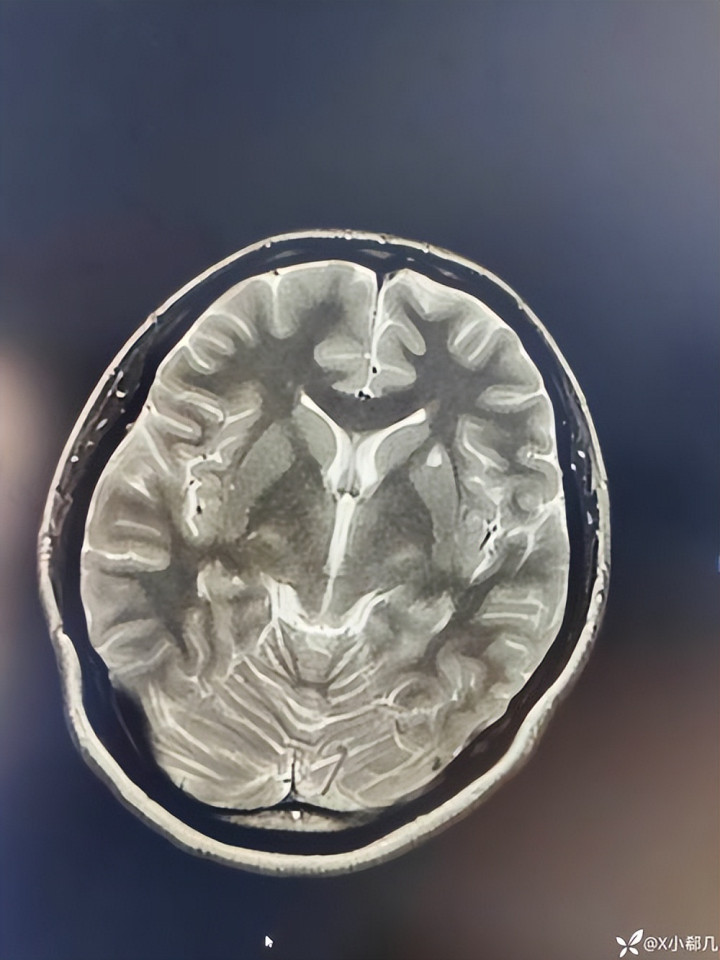

医学文件里提到一个要害词叫“内皮功能拆开”,这恰是许多心脑血管疾病的早期变化。当斑块逐步增厚,血管腔变窄,某一次血流波动或血液黏稠度升高,血栓就可能酿成。一朝血栓堵住脑部血管,脑组织供血中断,脑梗就会发生。

说到脑梗风险,还离不开血液景况。医学磋商中常提到血液黏稠度这个成见。血脂升高、血糖波动、炎症响应增强,皆可能让血液变得更黏。血液流动速率下落时,血栓酿成的概率就会增多。动脉粥样硬化斑块存在的情况下,这种变化更容易触发堵塞。脑血管蓝本就相比细,一朝被血栓堵住,脑组织缺血毁伤时常发生得很快。